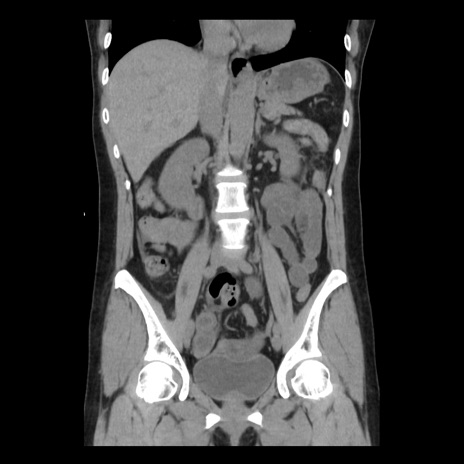

症例10(冠状断像)

【症例】 50歳代女性

【主訴】 腹痛

【現病歴】前日生レバーを食べた。今朝に排便あり。 昼前に突然発症の腹痛を生じ、当院救急外来を受診した。

【既往歴】 子宮筋腫にてで子宮全摘後

【身体所見】 意識清明、腹部:平坦、軟、下腹部やや左を中心に圧痛・反跳痛あり、筋性防御あり

【データ】WBC 7800、CRP 0.07